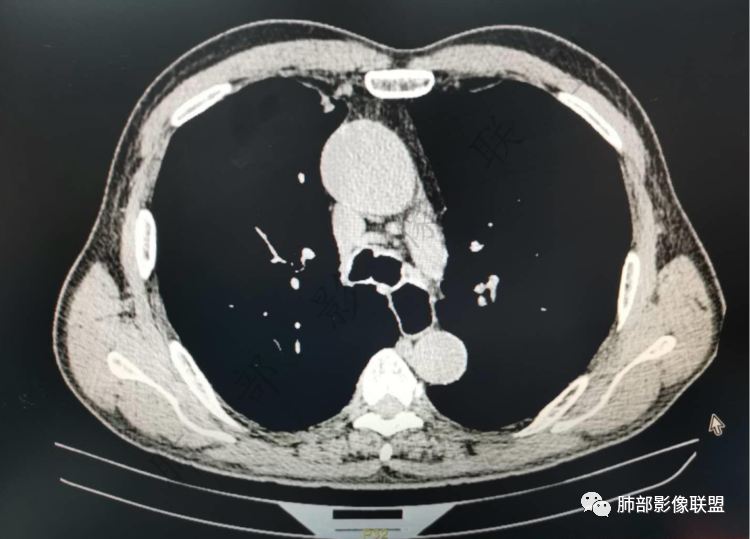

马春平(张家港市一院胸外科):

不要低估低分化鳞癌的倍增时间,近胸膜、生长快、坏死早。

这个鳞癌也太快了

必有路: 2个月这样进展

马春平(张家港市一院胸外科): @於雄 九江市一医院影像   上周开的一例鳞癌,82岁40天从直经2cm到4cm,体积增8倍

@赵承勇张家港澳洋医院   单发的炎性肉芽肿结节经过二个月时间出现倍增和坏死更难解释。

听禅观竹(赵承勇): @马春平(张家港市一院胸外科) 倍增的速度特别快的情况,接触到的小细胞和低分化腺癌的多,鳞癌的相对少

王武章: 所谓倍增时间,我个人以为很多时候是容易误导人的一个概念,用增大一倍的平均时间去衡量个体,本身就有很大出入。肿瘤增长过程中,惰性增长过程往往很长,一旦增长,有很多是很快速的,因为是指数级。